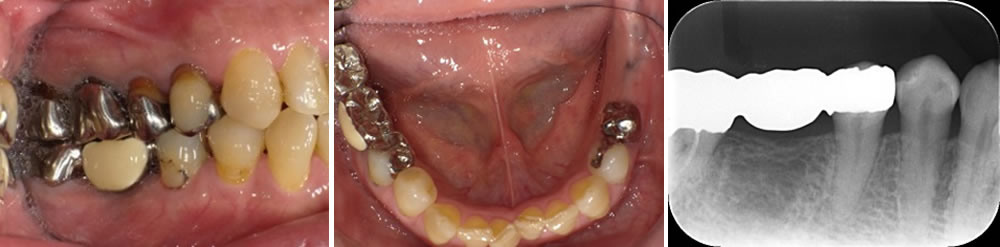

こちらの患者さまは、右下567部位(右下6欠損)にブリッジが装着されていましたが、経年によって適合が悪くなってきたため、再治療を行うこととなりました。

右下6の欠損部を補う治療法について、カウンセラーより各選択肢の説明を受けていただき、インプラント治療を選択されました。

事前にブリッジを除去し、支台歯となっていた右下5・7の虫歯治療を行いました。その後、CT撮影で骨の状態を確認し、服薬内容や手術の流れをご説明したうえで、手術日を決定しました。